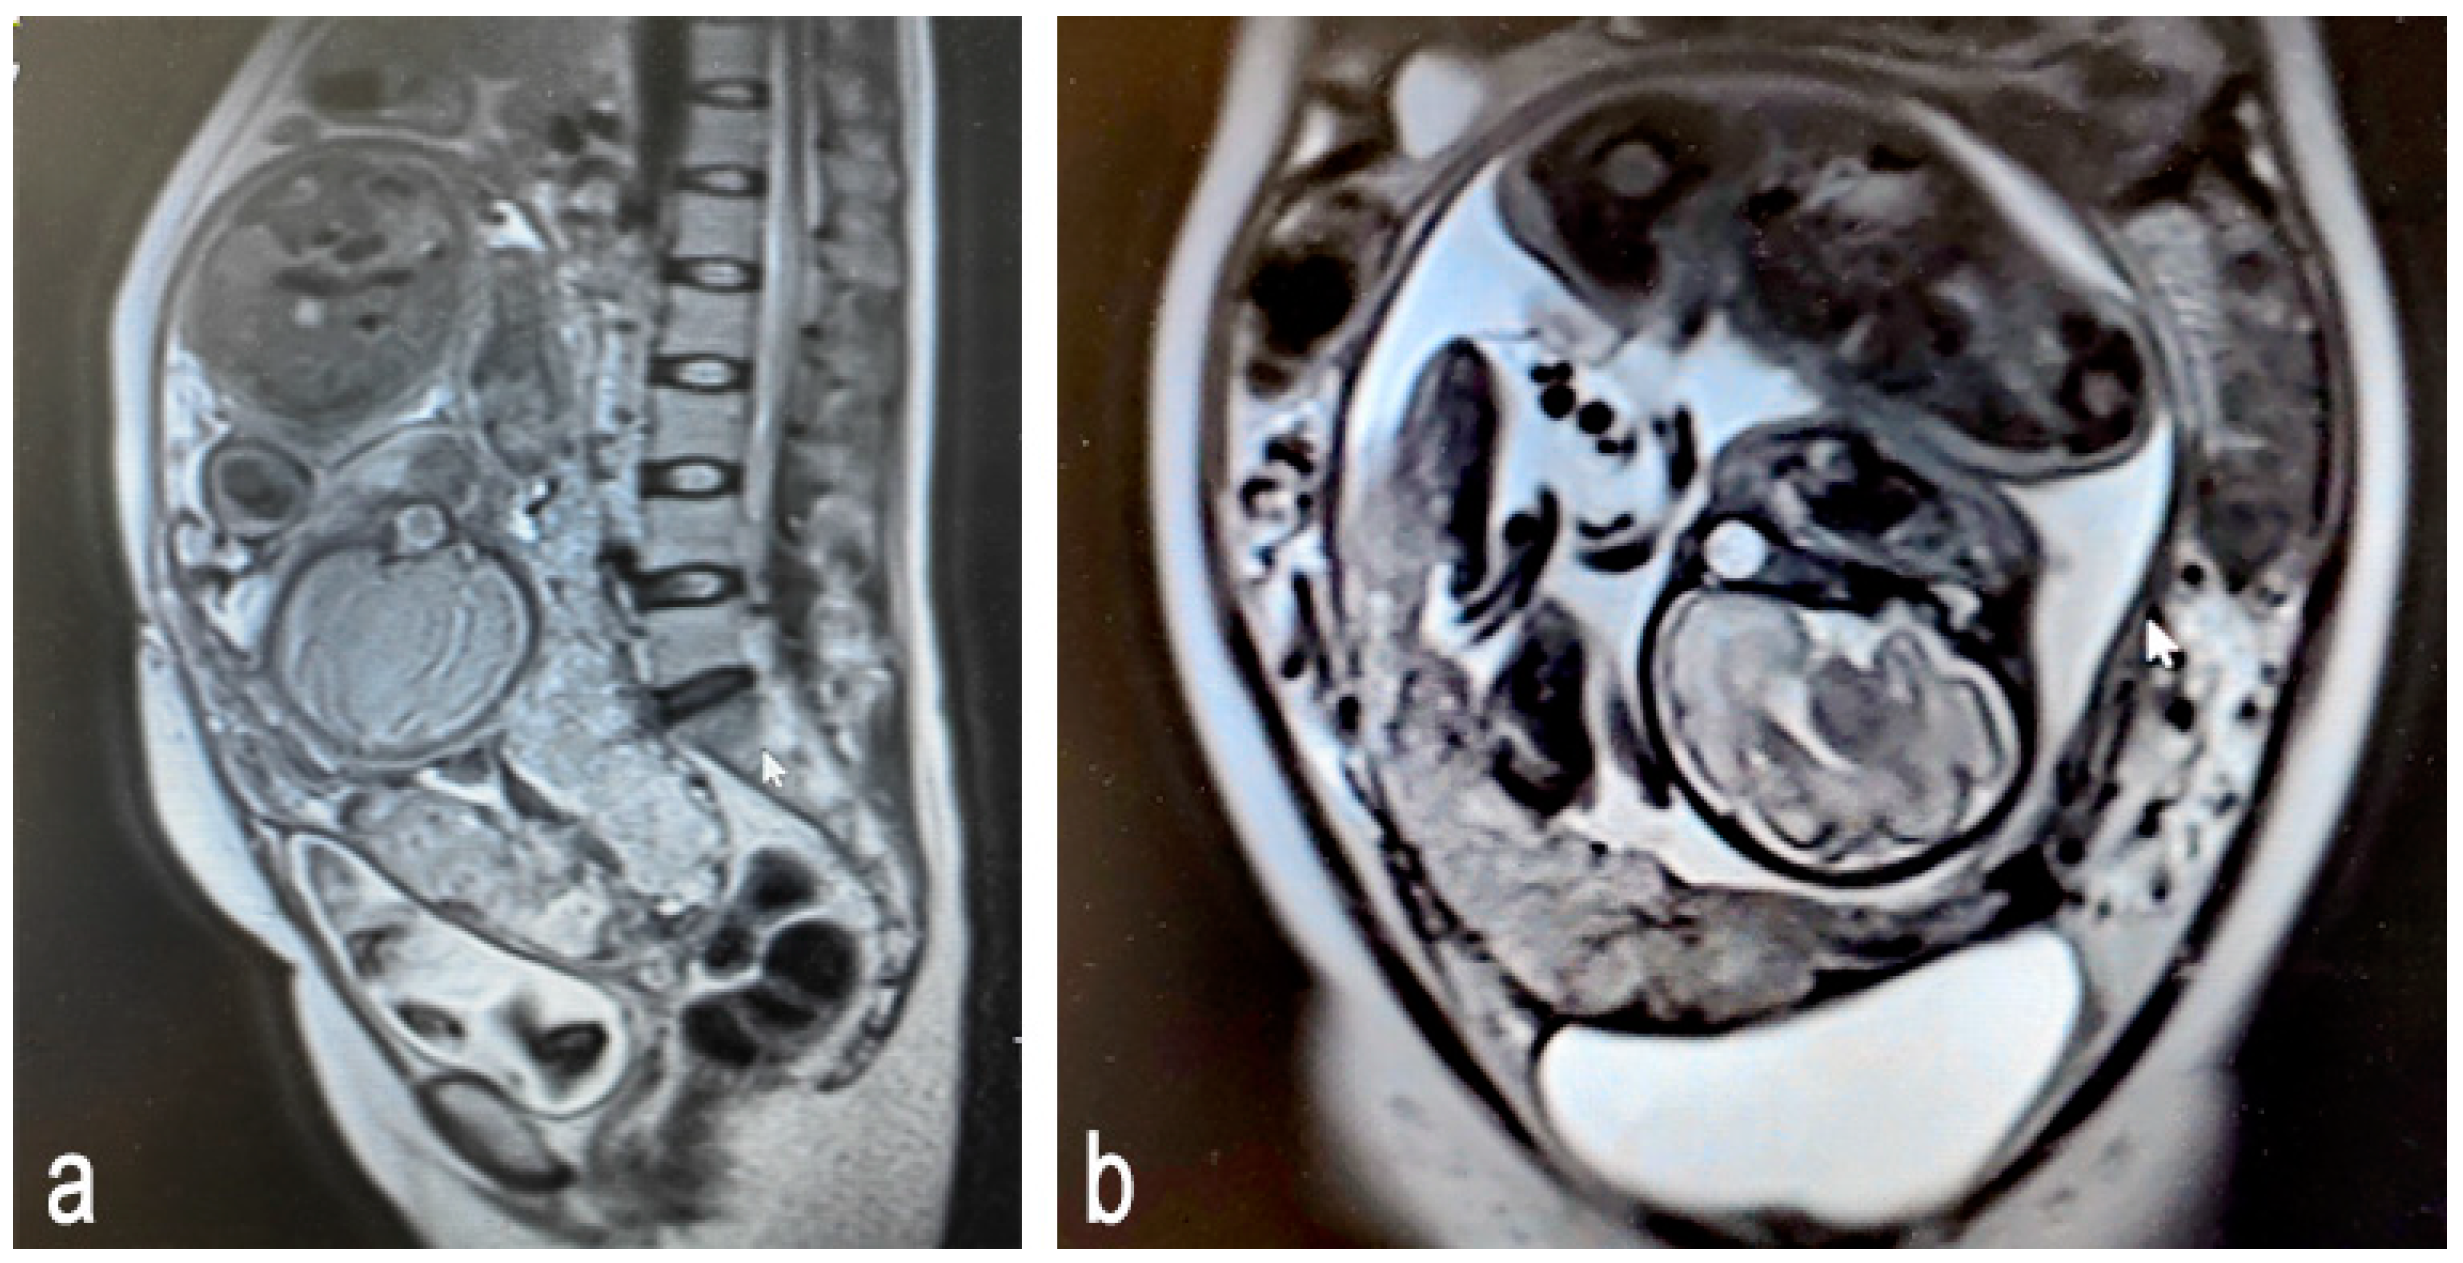

Figure 3.

Magnetic resonance images of placenta accreta spectrum (Prenatal stage): (a) sagittal plane; (b) frontal plane.

In the second and third trimesters, the placenta has fully developed, allowing MRI’s high resolution to accurately depict the depth and extent of placental invasion. Compared to ultrasound, MRI provides clearer anatomical structural information, thus revealing detailed relationships [36].The common features of PAS detected using MRI include the loss or blurring of the placenta–myometrium boundary: in cases of abnormal attachment or invasive implantation, the normal boundary (low signal line) between the placenta and myometrium becomes blurred or disappears completely. T2-weighted images show the loss of definition between the placenta and myometrium. Severe cases may show direct penetration through the myometrium (Figure 3).